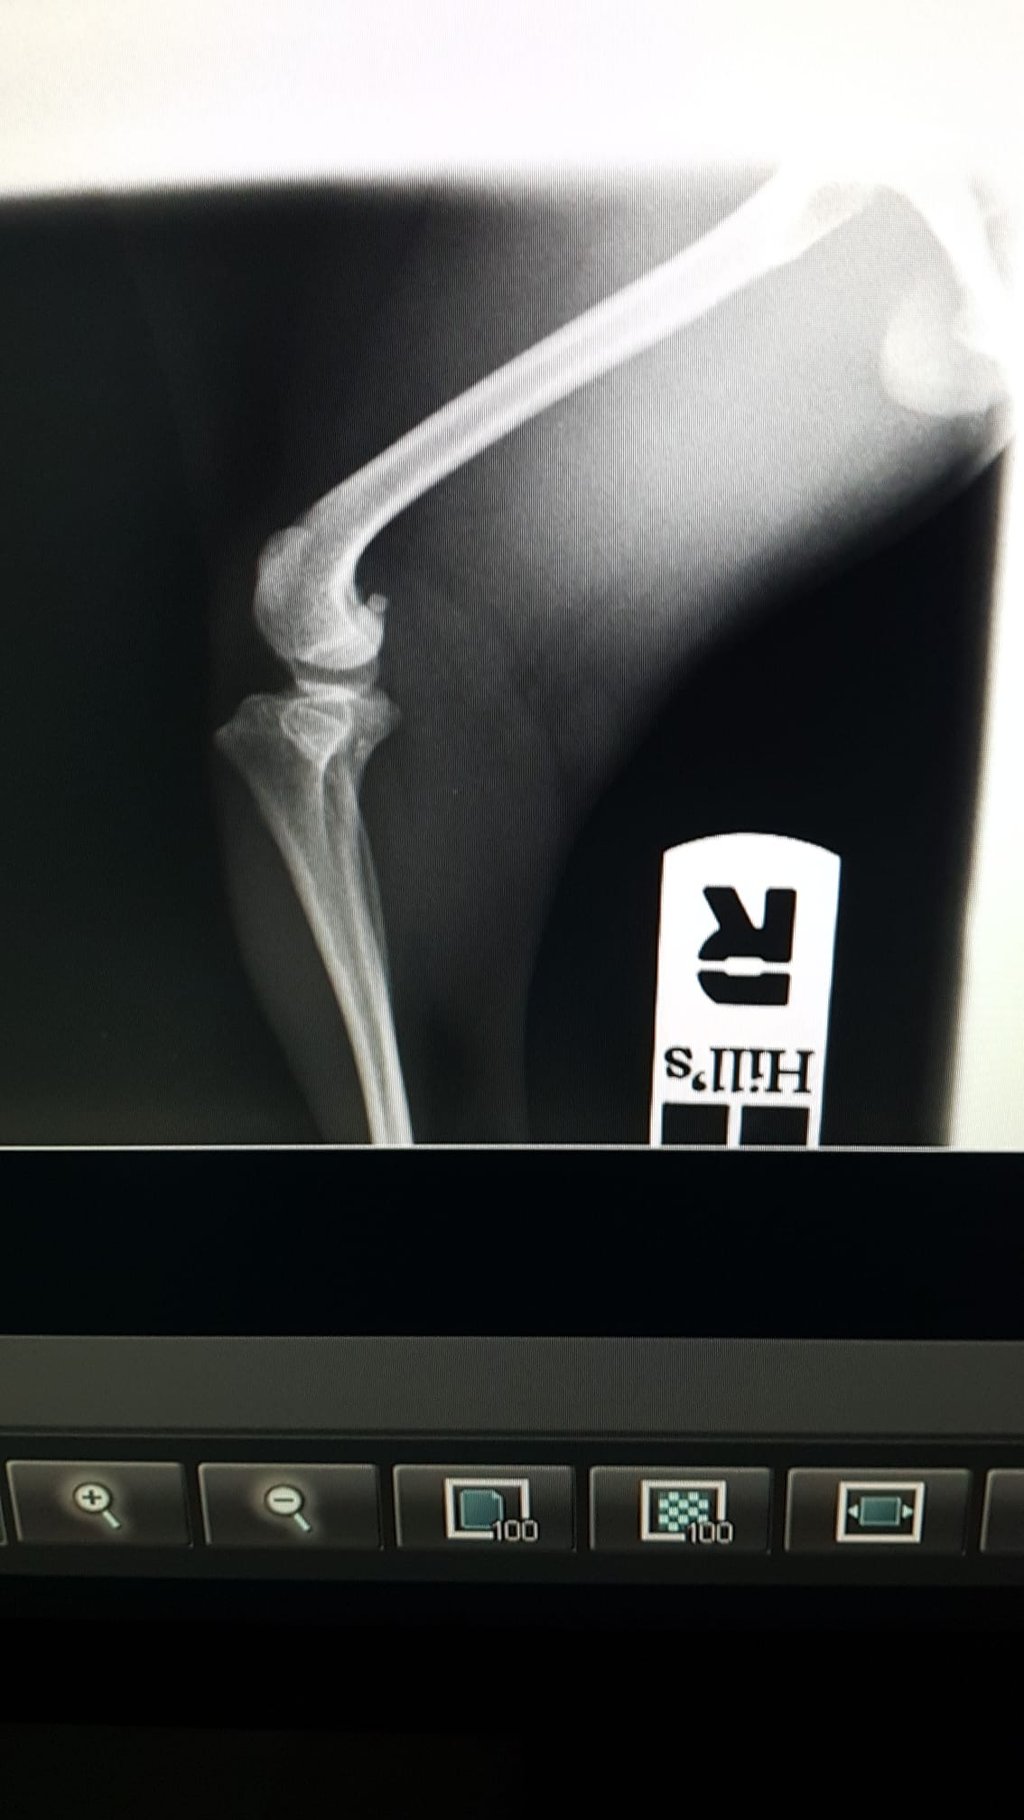

Nach dem Röntgen wurde eine Patellaluxation der Klasse IV diagnostiziert. Das ist eine Verlagerung der Kniescheibe, die aus ihrer Gleitrinne springt und so den natürlichen Bewegungsablauf beeinträchtigt. In den meisten Fällen ist eine Operation nötig, um die Kniescheibe in ihre ursprüngliche Position zurück zu führen und dort zu halten. Zusätzlich müssen Korrekturen von Unter- und Oberschenkel vorgenommen werden, um die Anatomie so weit zu verändern, dass die Kniescheibe dauerhaft in ihrer Führungsrinne verbleibt. Hierbei wird aus krummen Knochen ein Keil gesägt und der Knochen wird gerade wieder zusammengeschraubt (Osteotomie).